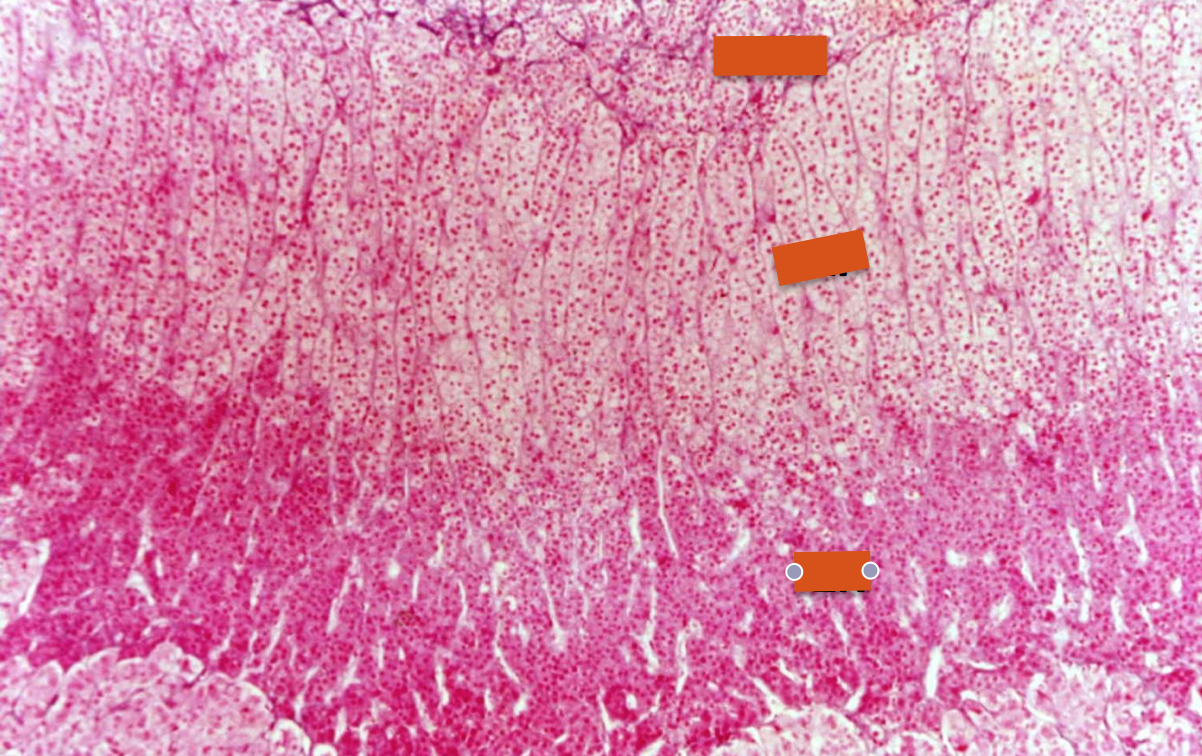

adrenal gland

adrenal gland: cortex

ZG=zona glomerulosa

ZF=zona fasciculata

ZR= zona reticularis